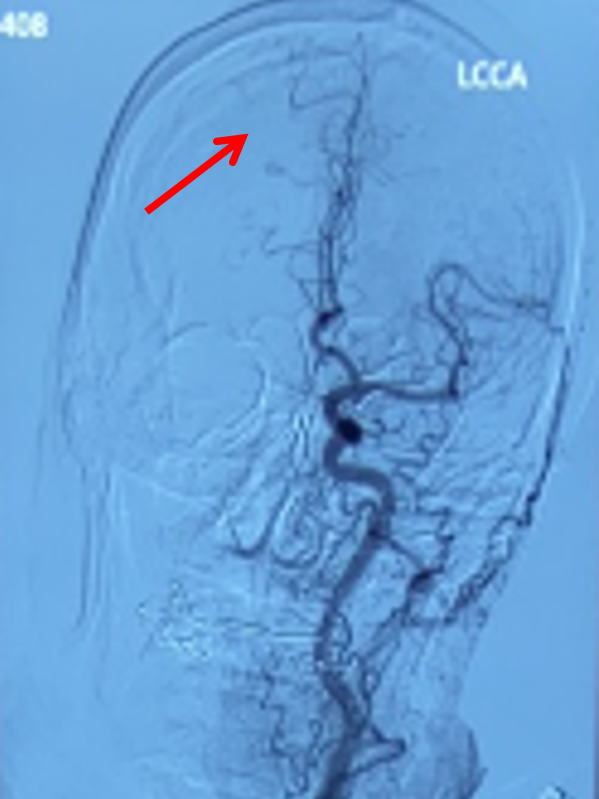

左侧颈总动脉正位造影:双侧大脑前动脉显影,且右侧大脑前动脉通过软膜吻合向右侧大脑中动脉支配区域供血(箭头示)。

中间导管到位后造影,提示右侧大脑中动脉M1段闭塞,右侧大脑中动脉供血区域通过右侧大脑前动脉软膜支部分代偿。